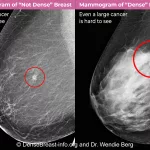

MRI (Magnetic Resonance Imaging) is the gold standard. It offers detailed pictures of soft tissue, shows the tumor’s size, shape, and exact location, and can even hint at its grade based on contrast enhancement patterns.

Advanced MRI techniques—like diffusion‑weighted imaging and MR spectroscopy—help differentiate low‑grade from high‑grade lesions before a biopsy.